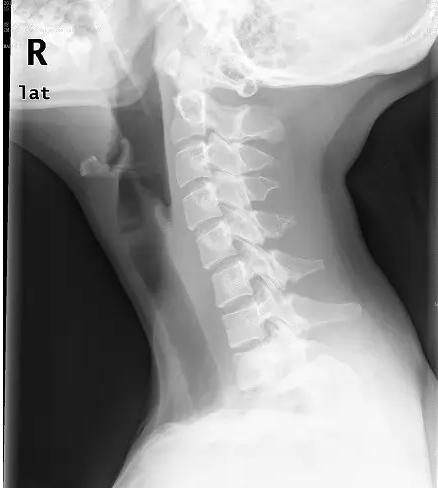

近日门诊接诊了一位18岁的花季少女小美,说是颈部疼痛难忍,已经半个月了,实在疼的不行了才来医院看看。拍片后显示:颈椎退变,生理弧度消失、变直。下面这张就是小张的颈椎侧位片。片子上,颈椎排列略呈“S”形。而不象是正常的“C”形。

有点医学常识的人都知道,正常脊柱由颈椎、胸椎、腰椎、骶尾椎组成。每一段都有相应的弯曲。其中颈椎前凸、胸椎是后凸,腰椎是前凸,骶尾椎又是后凸。

这样,整个脊柱就有一定的弹性,人在运动时脊柱上受力就有一定的缓冲,同时便于发力,就像撑杆跳高的杆子一样。如果颈椎的生理弧度减少、变直、甚至反屈畸形,就不能发挥上述作用,长此以往,就会加速颈椎间盘的退变,加速颈椎骨质增生,最终造成严重的颈椎病。